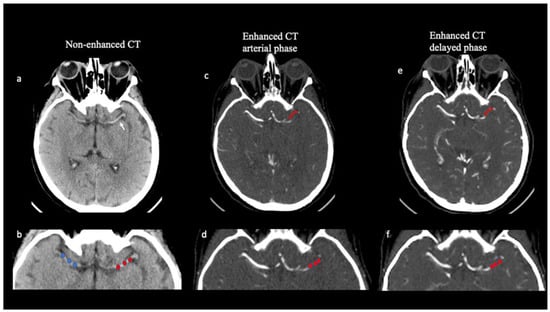

On NCCT imaging, the thrombus HU value was calculated by placing three spherical regions of interest (ROIs) within the thrombus location (size 3 × 3 voxels) (proximal, middle, and distal clot segment) but away from the boundaries of the thrombus (Figure 1). HU values were also calculated, using ROIs placed in three corresponding locations, on the contralateral artery to correct for the variability of hematocrit levels. The mean thrombus attenuation on NCCT was calculated by averaging the HU of the three ROIs both in the thrombosed and the contralateral arteries. On NCCT, thrombus average attenuation measurement (dHU) was calculated as the difference between the thrombus HU average value (tHU) and the HU average value on the contralateral side (cHU).

Thrombus attenuation measurements and thrombus perviousness quantification. Axial non-contrast CT (NCCT; a,b) demonstrates a hyperattenuating (“dense”) middle cerebral artery (MCA) (white arrow in a) in a 67-year-old patient with acute stroke. Thrombus attenuation measurement was calculated on NCCT as the difference between thrombus average density and contralateral artery by placing 3 spherical ROIs in the proximal, middle, and distal parts of the thrombus in the M1 segment of the left middle cerebral artery (red ROIs in b) and along the same vessel on the contralateral side (blue ROIs in b). Multiphase CTA (mCTA; c–f) identifies occlusion length of the M1 segment of the left middle cerebral artery, demonstrated as contrast-filling defects (square bracket in c,e). Three regions of interest (red ROIs) were placed in a left middle cerebral artery thrombus both in the arterial (c,d) and in the delayed phases (e,f) of the mCTA. Clot perviousness measurement was calculated as the difference in average thrombus attenuation measured on the arterial or delayed phase of mCTA and on NCCT.

The occlusion extension, defined as clot length, was determined based on the contrast-filling defects between the proximal and distal thrombus borders found on the delayed phase of CTA. Delayed phase images were chosen because they allowed the maximum amount of time to allow a contrast to reach the distal face of the clot from leptomeningeal collaterals. Mural calcifications were excluded from the analysis (Figure 1).

Thrombus HU average value was calculated both on NCCT and mCTA imaging. The clot perviousness measures the contrast penetration into a thrombus [20]. To estimate contrast penetration into the thrombus, the increase in the mean HU of the thrombus on mCTA was compared with the mean HU of the clot on NCCT. In the mCTA, two measurements of the average thrombus density were performed in the arterial and delayed phases, respectively, using the same method. Thrombus attenuation was measured both for the arterial (Perviousness pre-post 1) and delayed (Perviousness pre-post 2) phase of the mCTA (Figure 1).